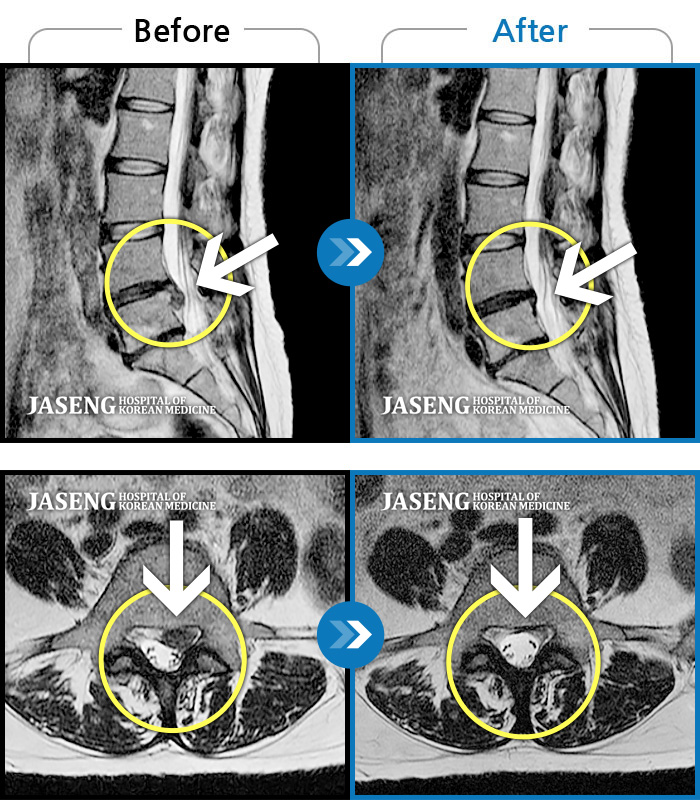

허리디스크

인천 · 조남훈 원장

허리가 너무 아프고 다리가 저려요.

촬영시기

2018.04.23 ~ 2025.12.05

2025.12.19